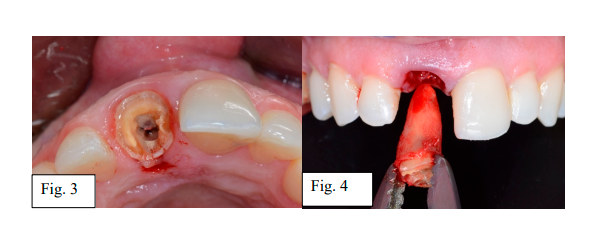

A paciente TAC, 39 anos, sexo feminino, procurou clínica privada com história de trauma bucal e posterior soltura da coroa do dente 11 (Fig. 1). Após avaliação clínica e tomográfica, foi diagnosticado fratura radicular. Dessa forma, seguiu-se com o planejamento para instalação de implante imediato com planejamento virtual e impressão de guia cirúrgica para instalação guiada com kit de Cirurgia Guiada da Implacil (Fig. 2).

Para o tratamento, foram seguidas todas as condutas cirúrgicas recomendadas na zona anterior da maxila, especialmente em pacientes com expectativa de excelência no resultado estético. Primeiramente, a exodontia com menor trauma possível (Fig. 3 e 4).